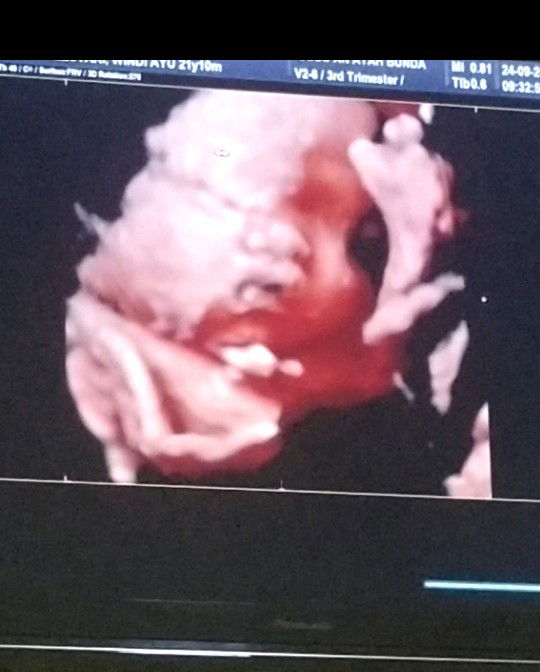

hey Bund tolong respon nya donk kmren aku USG 4D hasil USG nya sprti ini menurut ku bibir atas nya lebih tggi dari hidung nya v anak pertama ku bibir ny ga bgtu Bun ada ga yang sama dengan ku hasil USG nya bgtu bagai mana dengan bayi udh lahir nya apakah tetap bgtu ? mohon respon nya bunda2 cantik